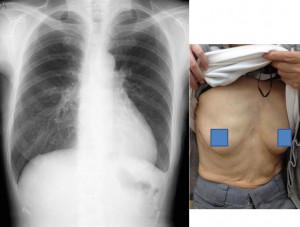

来院時、心尖部に4度の収縮期雑音あり、腋かへの放散が見られました。僧帽弁閉鎖不全症の所見です。胸部X線でも心拡大がありました(写真右上)。